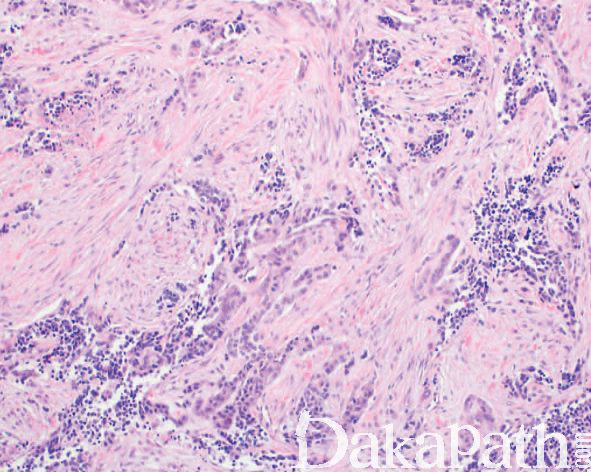

细胞巢之间可见致密的纤维结缔组织,位于颅面部的肿瘤常可见到骨小梁浸润;

有些病例假腺泡状结构不明显,主要由不规则片状、巢状或梁束状的色素性上皮细胞组成;

少数病例主要由呈挤压状的管状结构组成,仅含有很少的小圆细胞。